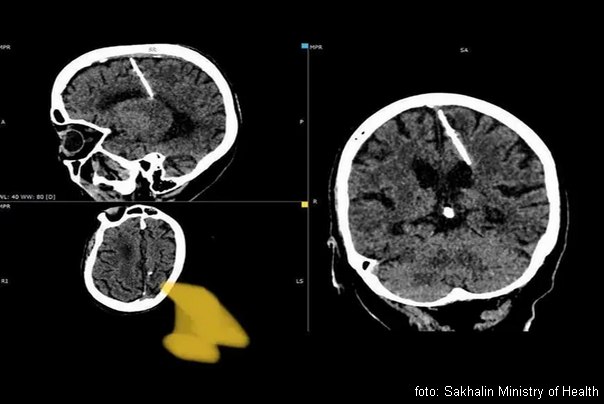

NEVEROVATNO! Ruskinja živela 80 godina sa iglom u mozgu!

Jedna starija žena – ruskinja, na dalekom istoku Rusije živela je ceo život sa iglom dugom u mozgu, otkriveno je nakon što su lekari došli do neočekivanog otkrića tokom CT skeniranja….

Lokalno zdravstveno odeljenje regiona Sahalin , veruje da je 80-godišnja žena bila žrtva neuspelog čedomorstva od strane njenih roditelja tokom Drugog svetskog rata. Lekari su takođe rekli su da neće pokušati da uklone iglu iz straha da će joj pogoršati stanje.

„Takvi slučajevi tokom godina gladi nisu bili neuobičajeni.“ Njeni roditelji su verovatno odlučili da svoje dete ubiju tokom Drugog svetskog rata kao što je ona bila. živeći sa iglom dugom 3 cm „od rođenja“. Ovaj metod se često koristio da bi se sakrili dokazi o zločinu, navodi se u saopštenju.

„Igla joj je ušla u levi parijetalni režanj, ali nije dala željeni efekat – devojčica je preživela“, dodaju u tamošnjem zdravstvu i dodaju da se pacijentkinja nikada nije žalila na glavobolje zbog povrede i da nije životno ugrožena izveštava gardijan